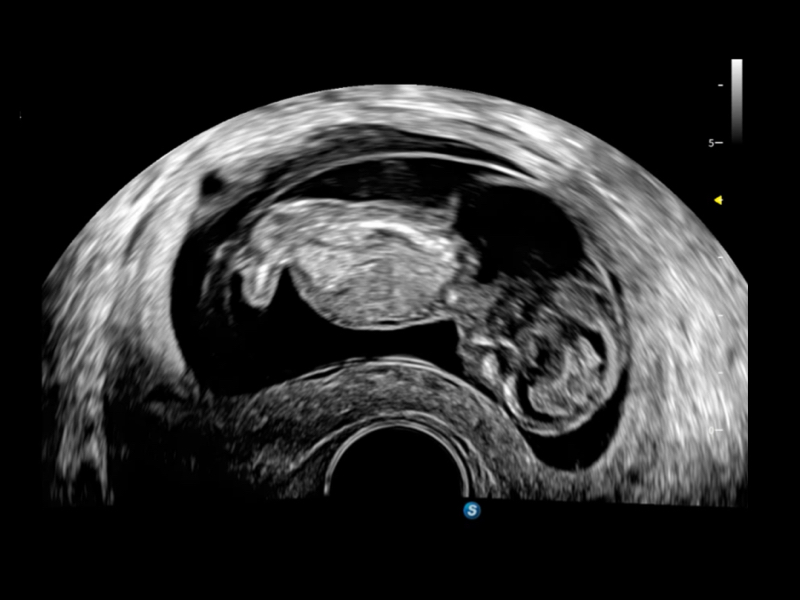

作为开立医疗全新打造的超高端旗舰超声产品,从探头抬起唤醒开启扫查到多维探头发射接收,通过先进的场成像发射、自适应聚合重建等技术,基于RF Data原始射频数据在图像生成、高端功能等方面实现突破,提供多科室综合临床解决方案。

S80 提供多样化超声成像技术,可满足不同科室的需求,在助力扫查诊断和介入治疗中发挥着重要作用。